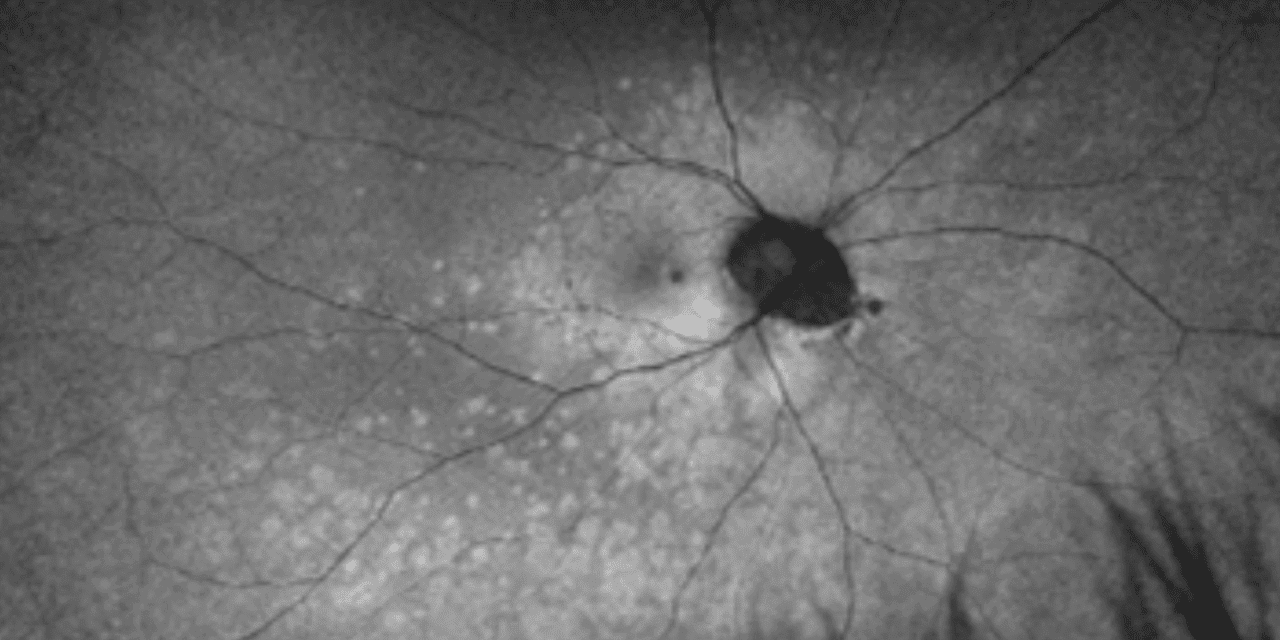

The patient presented one week later with worsening paracentral vision loss, which he described as “constant but inconsistent” scintillating vision loss expanding and contracting throughout the day. He also reported a new onset of photopsia. The patient’s visual acuity remained 20/20 in each eye. The Amsler grid findings showed an increased relative scotoma surrounding central fixation compared to the previous scattered findings. Although the fundus appearance appeared relatively stable (Figures 1A and 1B), the FAF showed multiple dense, pinpoint, hyperfluorescent lesions surrounding the macula and extending into the posterior pole and midperiphery (Figures 1C and 1D). The macular SD-OCT images revealed increased disruption of the deep retinal and retinal pigment epithelium layers of the outer retinal layers, affecting the ellipsoid zone photoreceptors temporal to the foveal depression. Based on the SD-OCT outer retinal pathology and pathognomonic FAF appearance, the patient was diagnosed with MEWDS in his right eye.

Figure 1: UWF color photo of the right eye (A) and the left eye (B) shows no significant appearance of white lesions at 1 week follow up. WF FAF of the right eye (C) shows small hyperautofluorescent spots and dots in the paramacular area extending through the posterior pole into the midperiphery, no such lesions noted in the left eye (D)

Figure 3: Serial UWF FAF images of the right eye from 1 week (A), 1 month (B), and 3 month follow-ups (C) showing a generalized decrease in hyperautofluorescent lesions with time.